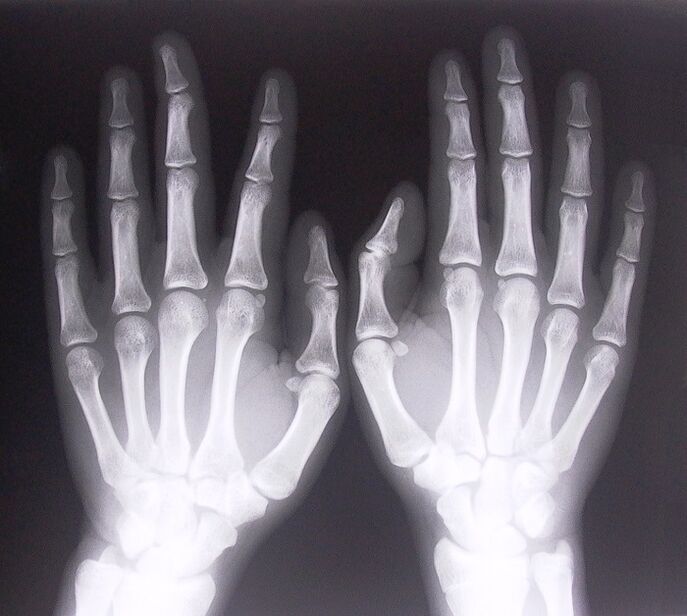

1. Πάρτε ακτινογραφίες.

Η ακτινογραφία ως τρόπος διάγνωσης του πόνου στις αρθρώσεις των δακτύλων